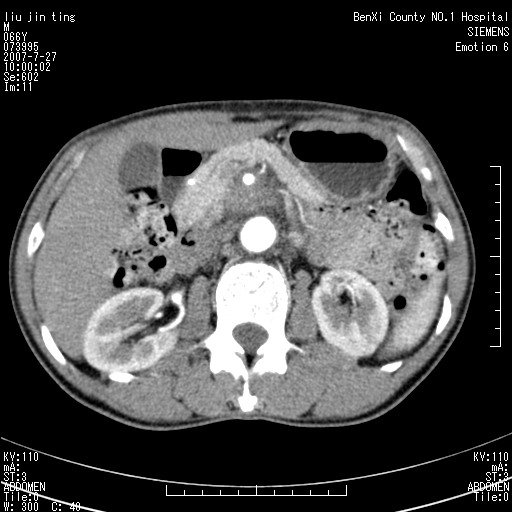

腹痛,背痛,无恶心呕吐,不黄,彩超示胰腺钩癌,ct扫描病灶平扫30-40hu,增强后动脉期40--60hu,静脉期50-68hu,真的是钩突上的么?您要试一试么?

动脉期

静脉期

沿着肠系膜上动脉呈匍匐性生长的软组织肿块,形态不规则,包绕肠系膜上动脉,呈明显强化,考虑来源于肠系膜的恶性肿瘤

沿着肠系膜上动脉呈匍匐性生长的软组织肿块,形态不规则,包绕肠系膜上动脉,呈轻-中度强化,考虑来源于肠系膜的恶性肿瘤。